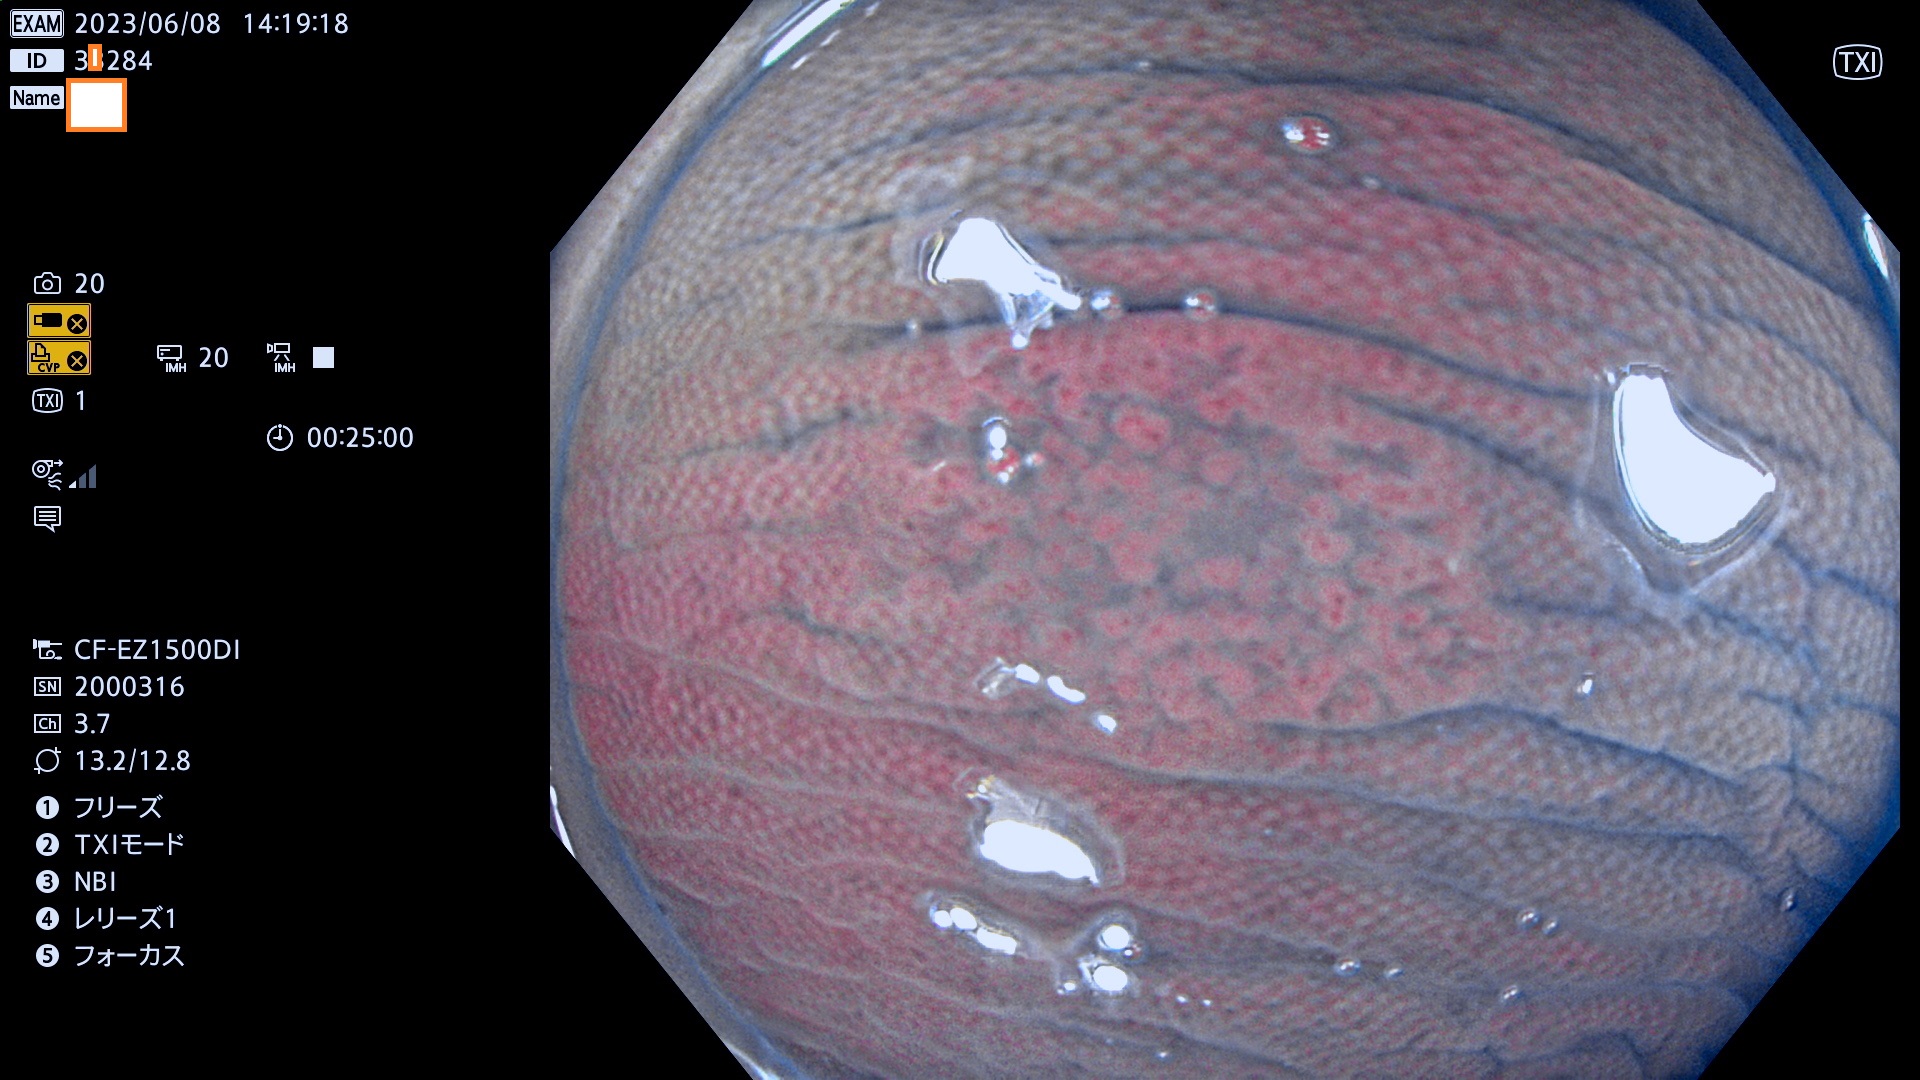

「表面型腫瘍」の中で、完全に平坦な物をUb、陥凹している物をUcと呼びます。平坦隆起型(Ua)よりも、発見が難しく危険な病変です。このタイプの発見率は「腺腫発見率」よりも、遥かに重要な意義があります。

抽出の対象期間 2023年6月8日(木)〜11(日)の4日間(48件の検査)